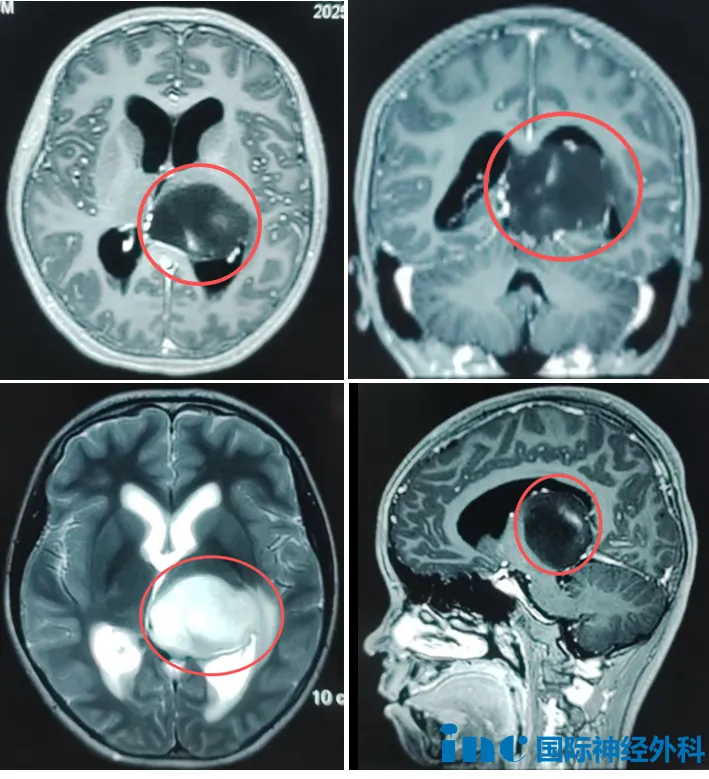

12歲的女孩諾諾,突發(fā)頭暈,嘔吐、食欲差,檢查發(fā)現(xiàn)左側(cè)丘腦占位,大小約37mm*45mm*40mm,三腦室受壓,兩側(cè)腦室增寬。對于諾諾父母而言,孩子確診腦瘤猶如晴天霹靂,恨不能立刻手術(shù)“一刀了斷”。然而,若巨大腫瘤位于大腦深部,又該如何抉擇?

左側(cè)丘腦占位